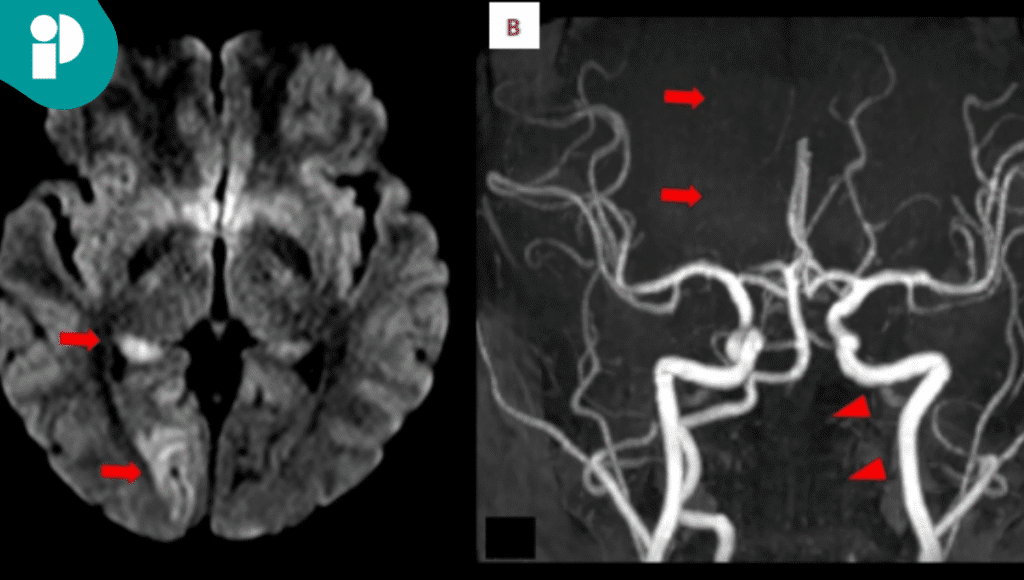

Dos días después presentó entumecimiento en el lado izquierdo y alteraciones visuales repentinas. Los estudios médicos confirmaron un infarto en el lóbulo occipital derecho y una disección de la arteria vertebral izquierda con trombo intramural.

Fue sometida de urgencia a una trombectomía endovascular y trombolisis intraarterial, con resultados positivos. Tras el tratamiento y una doble terapia antiplaquetaria, recuperó casi por completo sus funciones, quedando únicamente con un defecto visual leve.